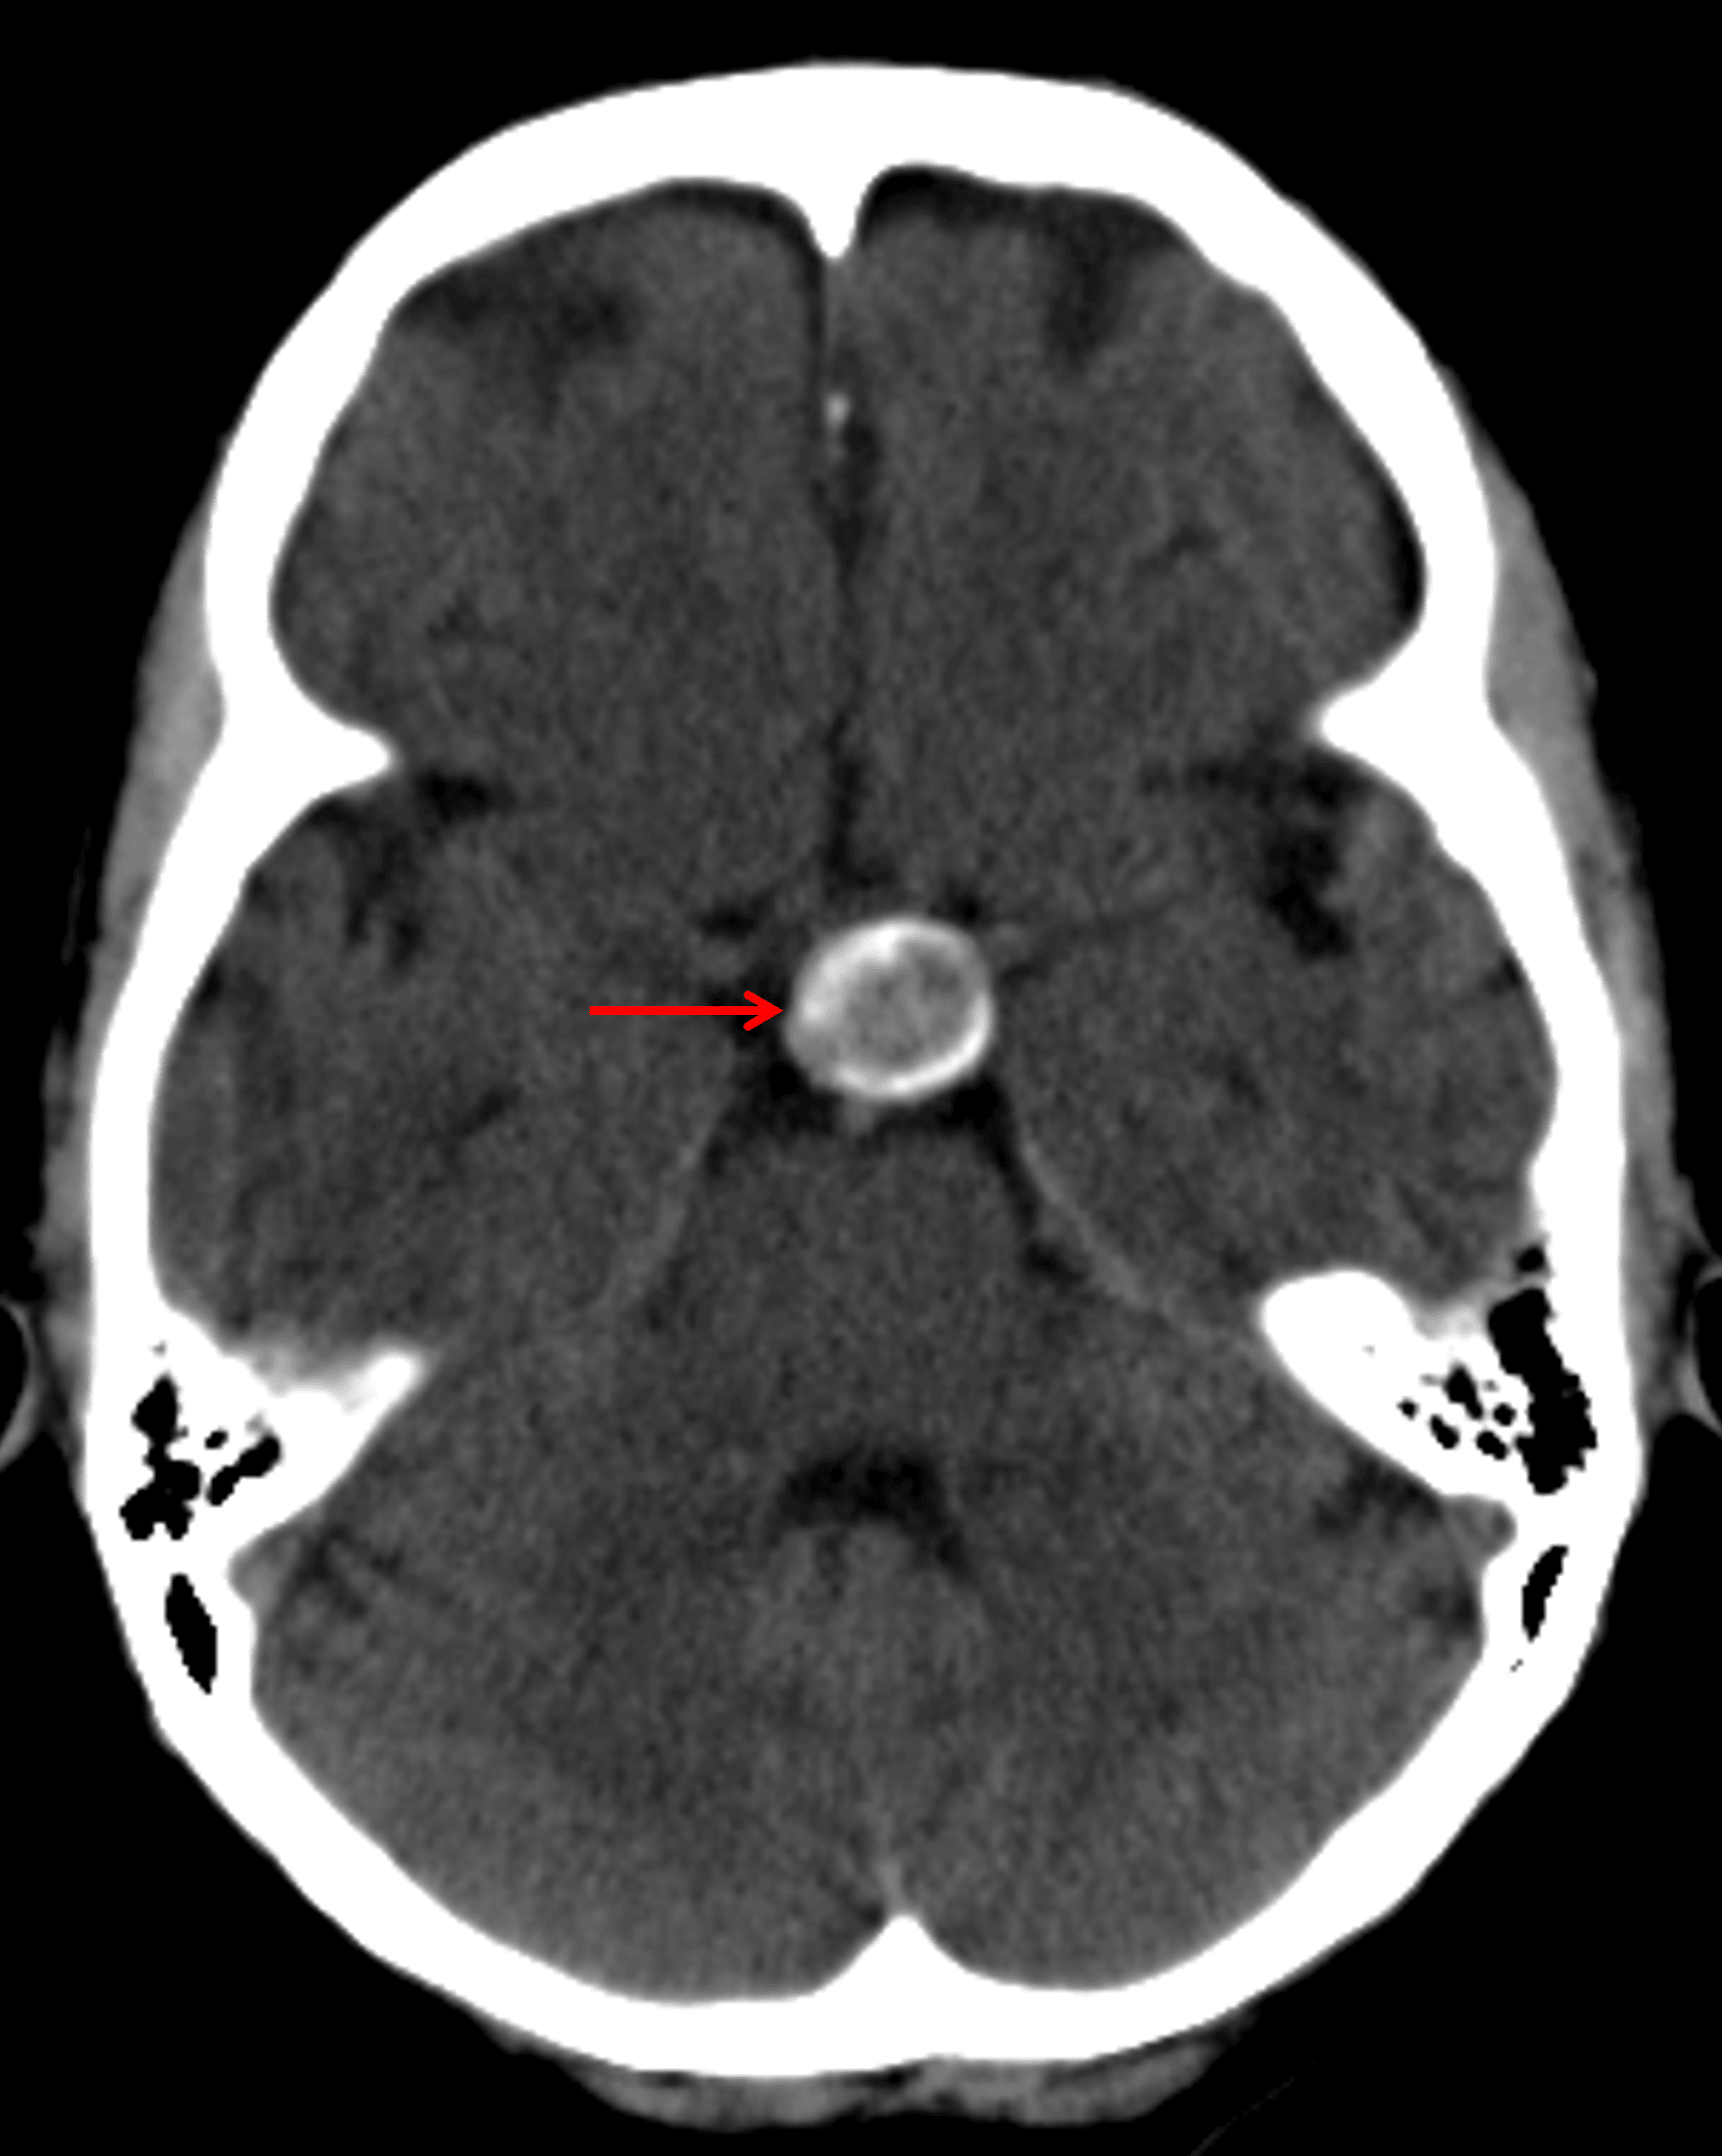

CT

- Calcified suprasellar mass

Calcified suprasellar mass (red arrow).